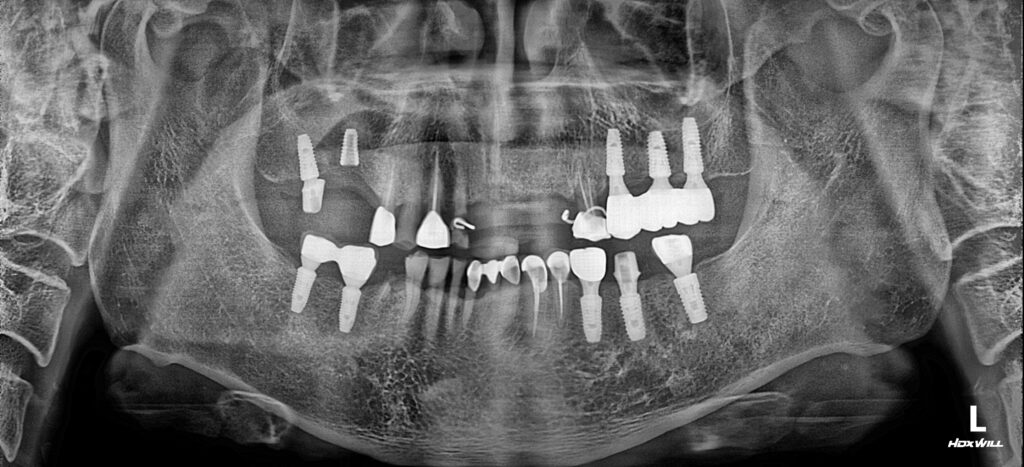

24.10.11

전체적인 치주질환, 우식치료, 임플란트를 진행하셨으나 바쁜 일정으로 내원을 못하셔서 늦게 오셔서 확인한 파노라마 방사선 사진입니다. 우측 아래 치아파절과 상악 앞니 임시보철물과 치아들까지 더 유지하기 어려운 상태로 내원하셨는데요.